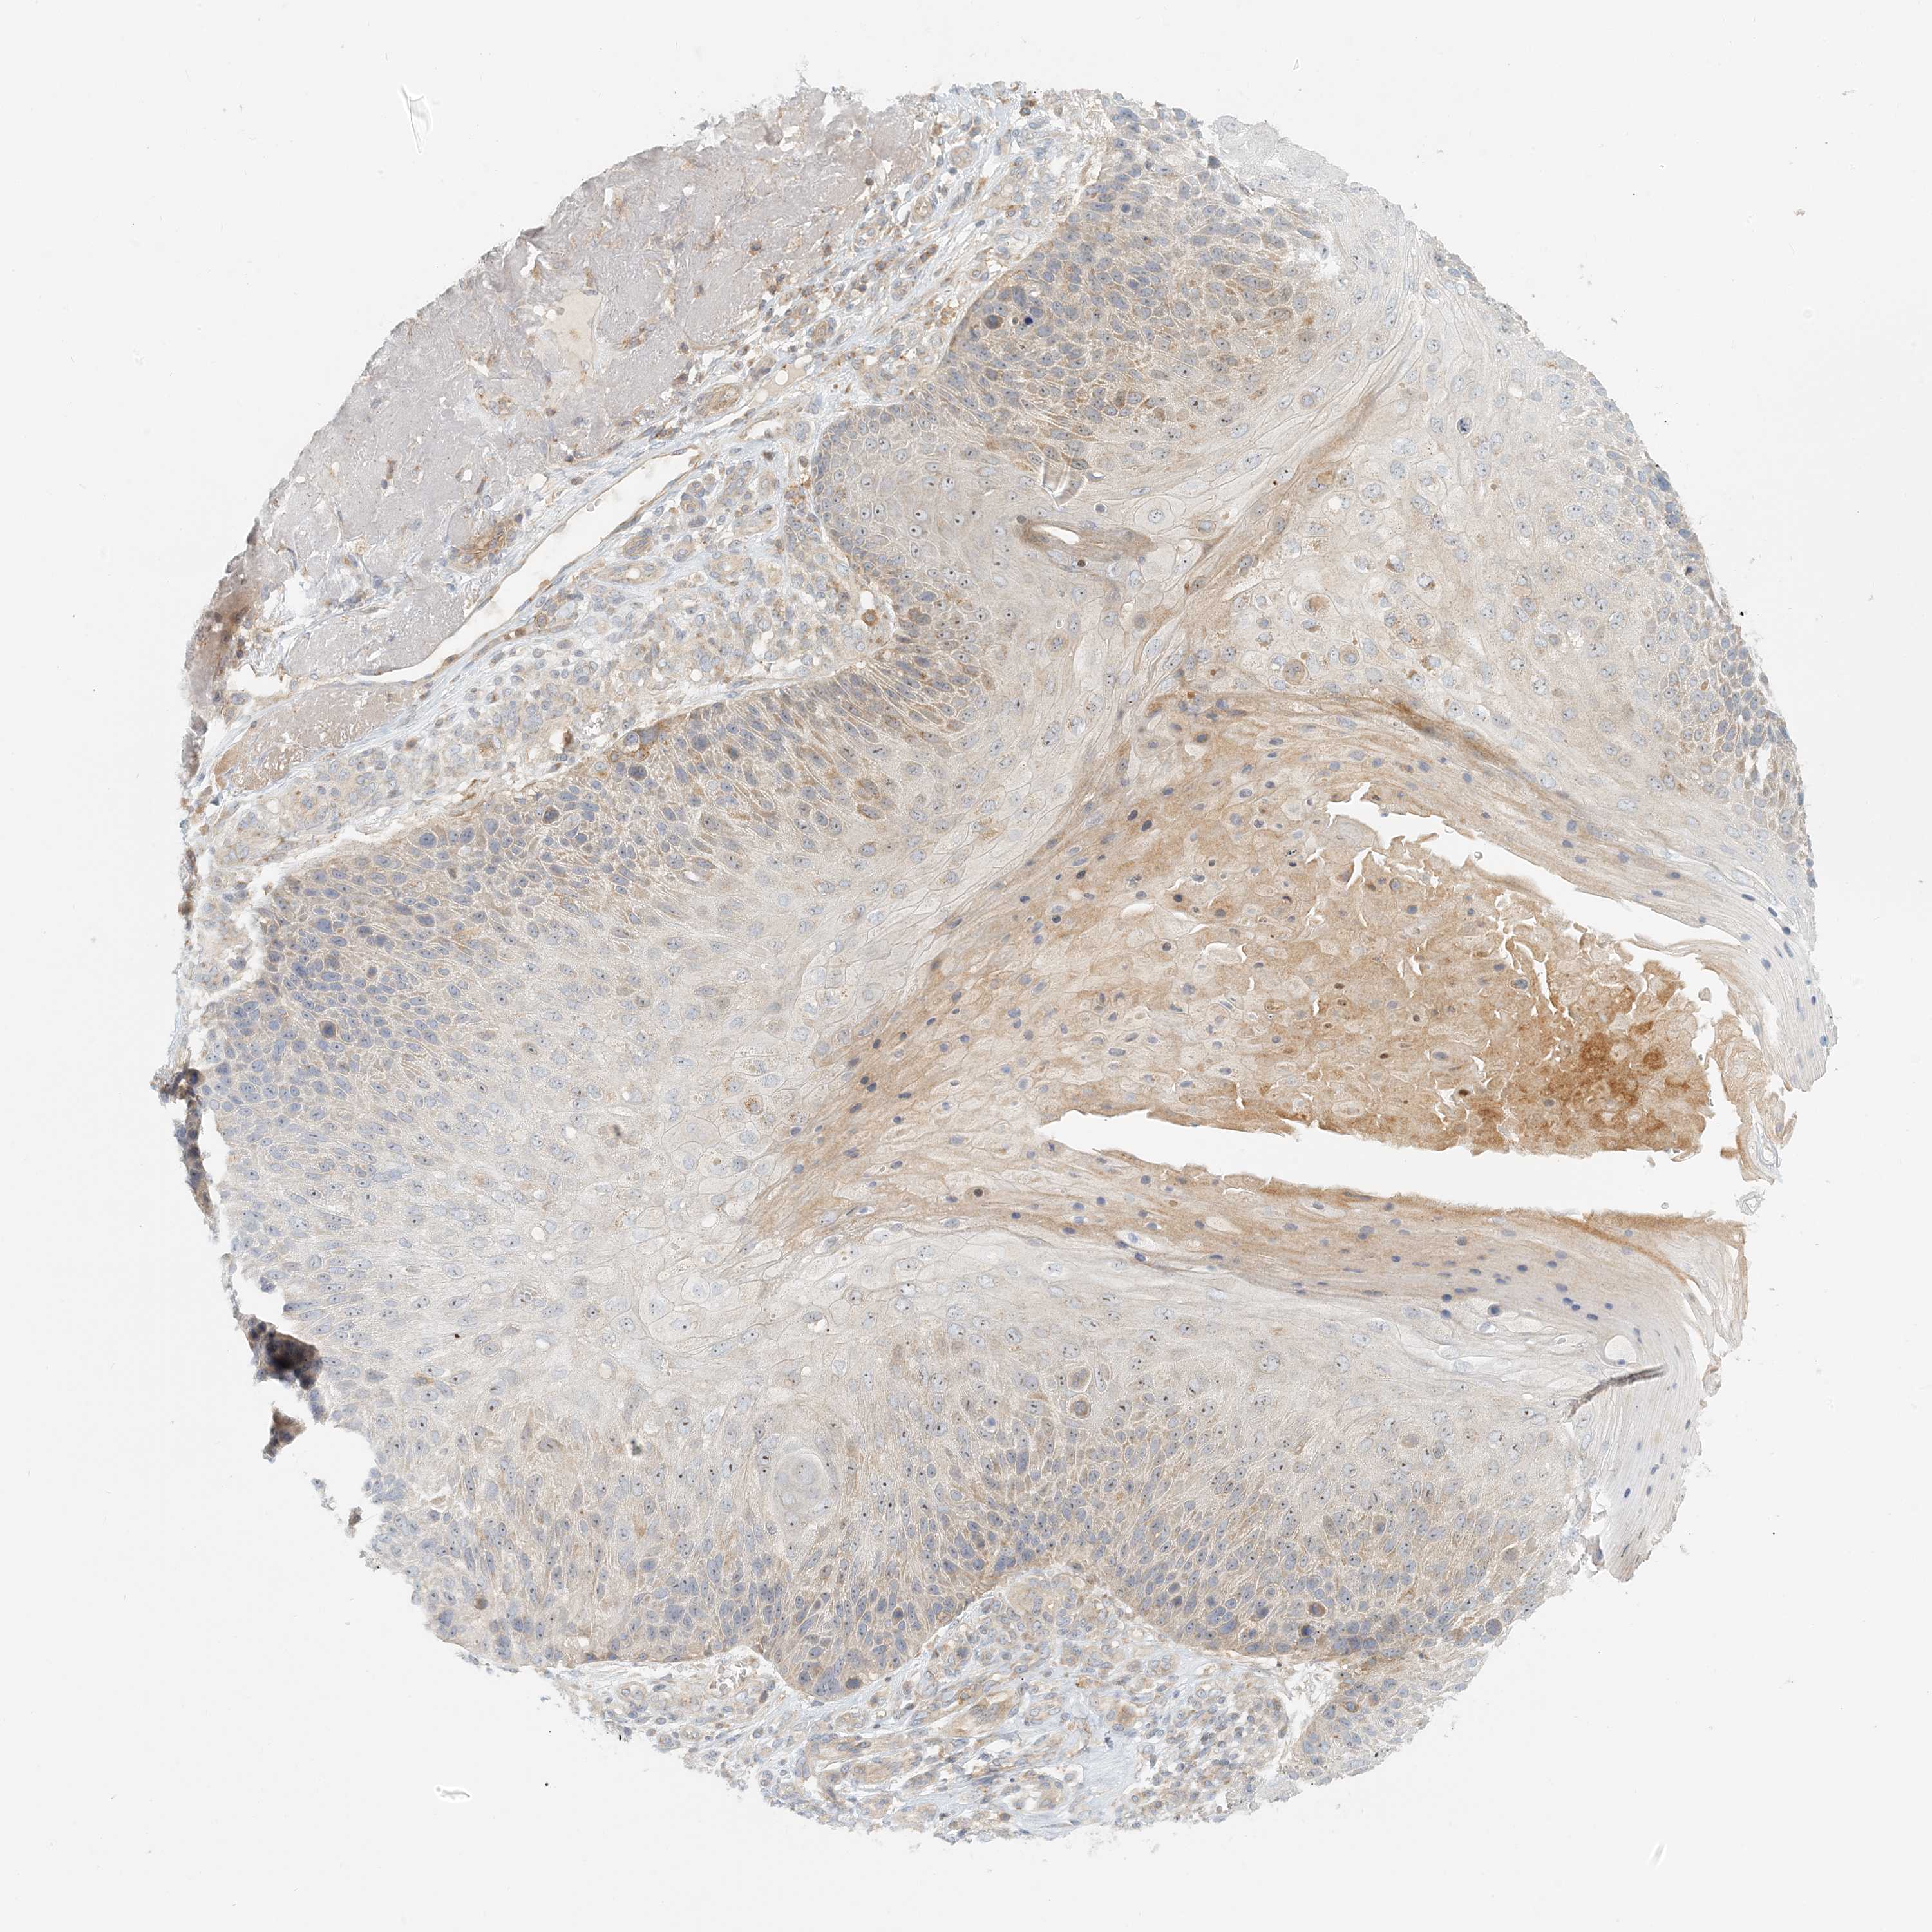

Basal cell and squamous cell cancer

SKIN CANCER - Protein expressioni

A mouse-over function shows sample information and annotation data. Click on an image to view it in a full screen mode. Samples can be filtered based on level of antibody staining by selecting one or several of the following categories: high, medium, low and not detected. The assay and annotation is described here.

Antibody stainingi

Antibody staining in the annotated cell types in the current human tissue is reported as not detected, low, medium, or high, based on conventional immunohistochemistry profiling in selected tissues. This score is based on the combination of the staining intensity and fraction of stained cells.

Each image is clickable and will lead to virtual microscopy that enables deeper exploration of all samples and also displays staining intensity scores, fraction scores and subcellular localization as well as patient and tissue information for each sample.

Antibody HPA035241

Staining

High

Medium

Low

Not detected

Intensity

Strong

Moderate

Weak

Negative

Quantity

>75%

75%-25%

<25%

None

Location

Nuclear

Cytoplasmic/membranous

Cytoplasmic/membranous,nuclear

Squamous cell carcinoma, NOS